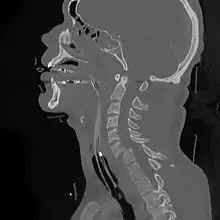

Sagittal reconstruction of a CT scan showing a cervical fracture with dislocation at the level of C6/7